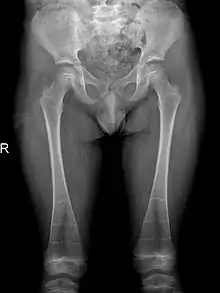

It is also reported that individuals may also have pelvic abnormalities. This includes the development of narrow iliac wings, as well as widened femoral necks. However, incidence of both symptoms are rare in patients with DSS, occurring in less than 30% of cases.[6][7]

The occurrence of DSS also leads to deformities of the limbs. 80% of patients reported with abnormalities of the metaphysis such as metaphyseal flaring, radiolucent metaphyses, abnormal metaphyseal trabeculation, which is abnormal trabecula patterns in the metaphyseal region, and epimetaphyseal sclerosis. Other limbic abnormalities include progressive bowing of long bones, which is present in rare cases.[6][7]

Sclerosis of epiphyses, diaphyses, and metaphyses with increased radiolucency are key characteristics of the disease.[18] In addition, mottled metaphyseal sclerosis and widening are also present in patients.[4][9] Development of irregular patchy sclerosis along the bone can also be identified,[9] as well as metaphyseal flaring evolve towards Erlenmeyer flask deformity with nonuniform patches of sclerosis, which are especially prevalent in older patients.[10]

The metadiaphyses, a portmanteau of the metaphysis and diaphysis,[20] are bulbous and expanded with bowing and relative radiolucency. The expanded regions are also sclerotic and gives the characteristic bone-in-bone appearance.[4]